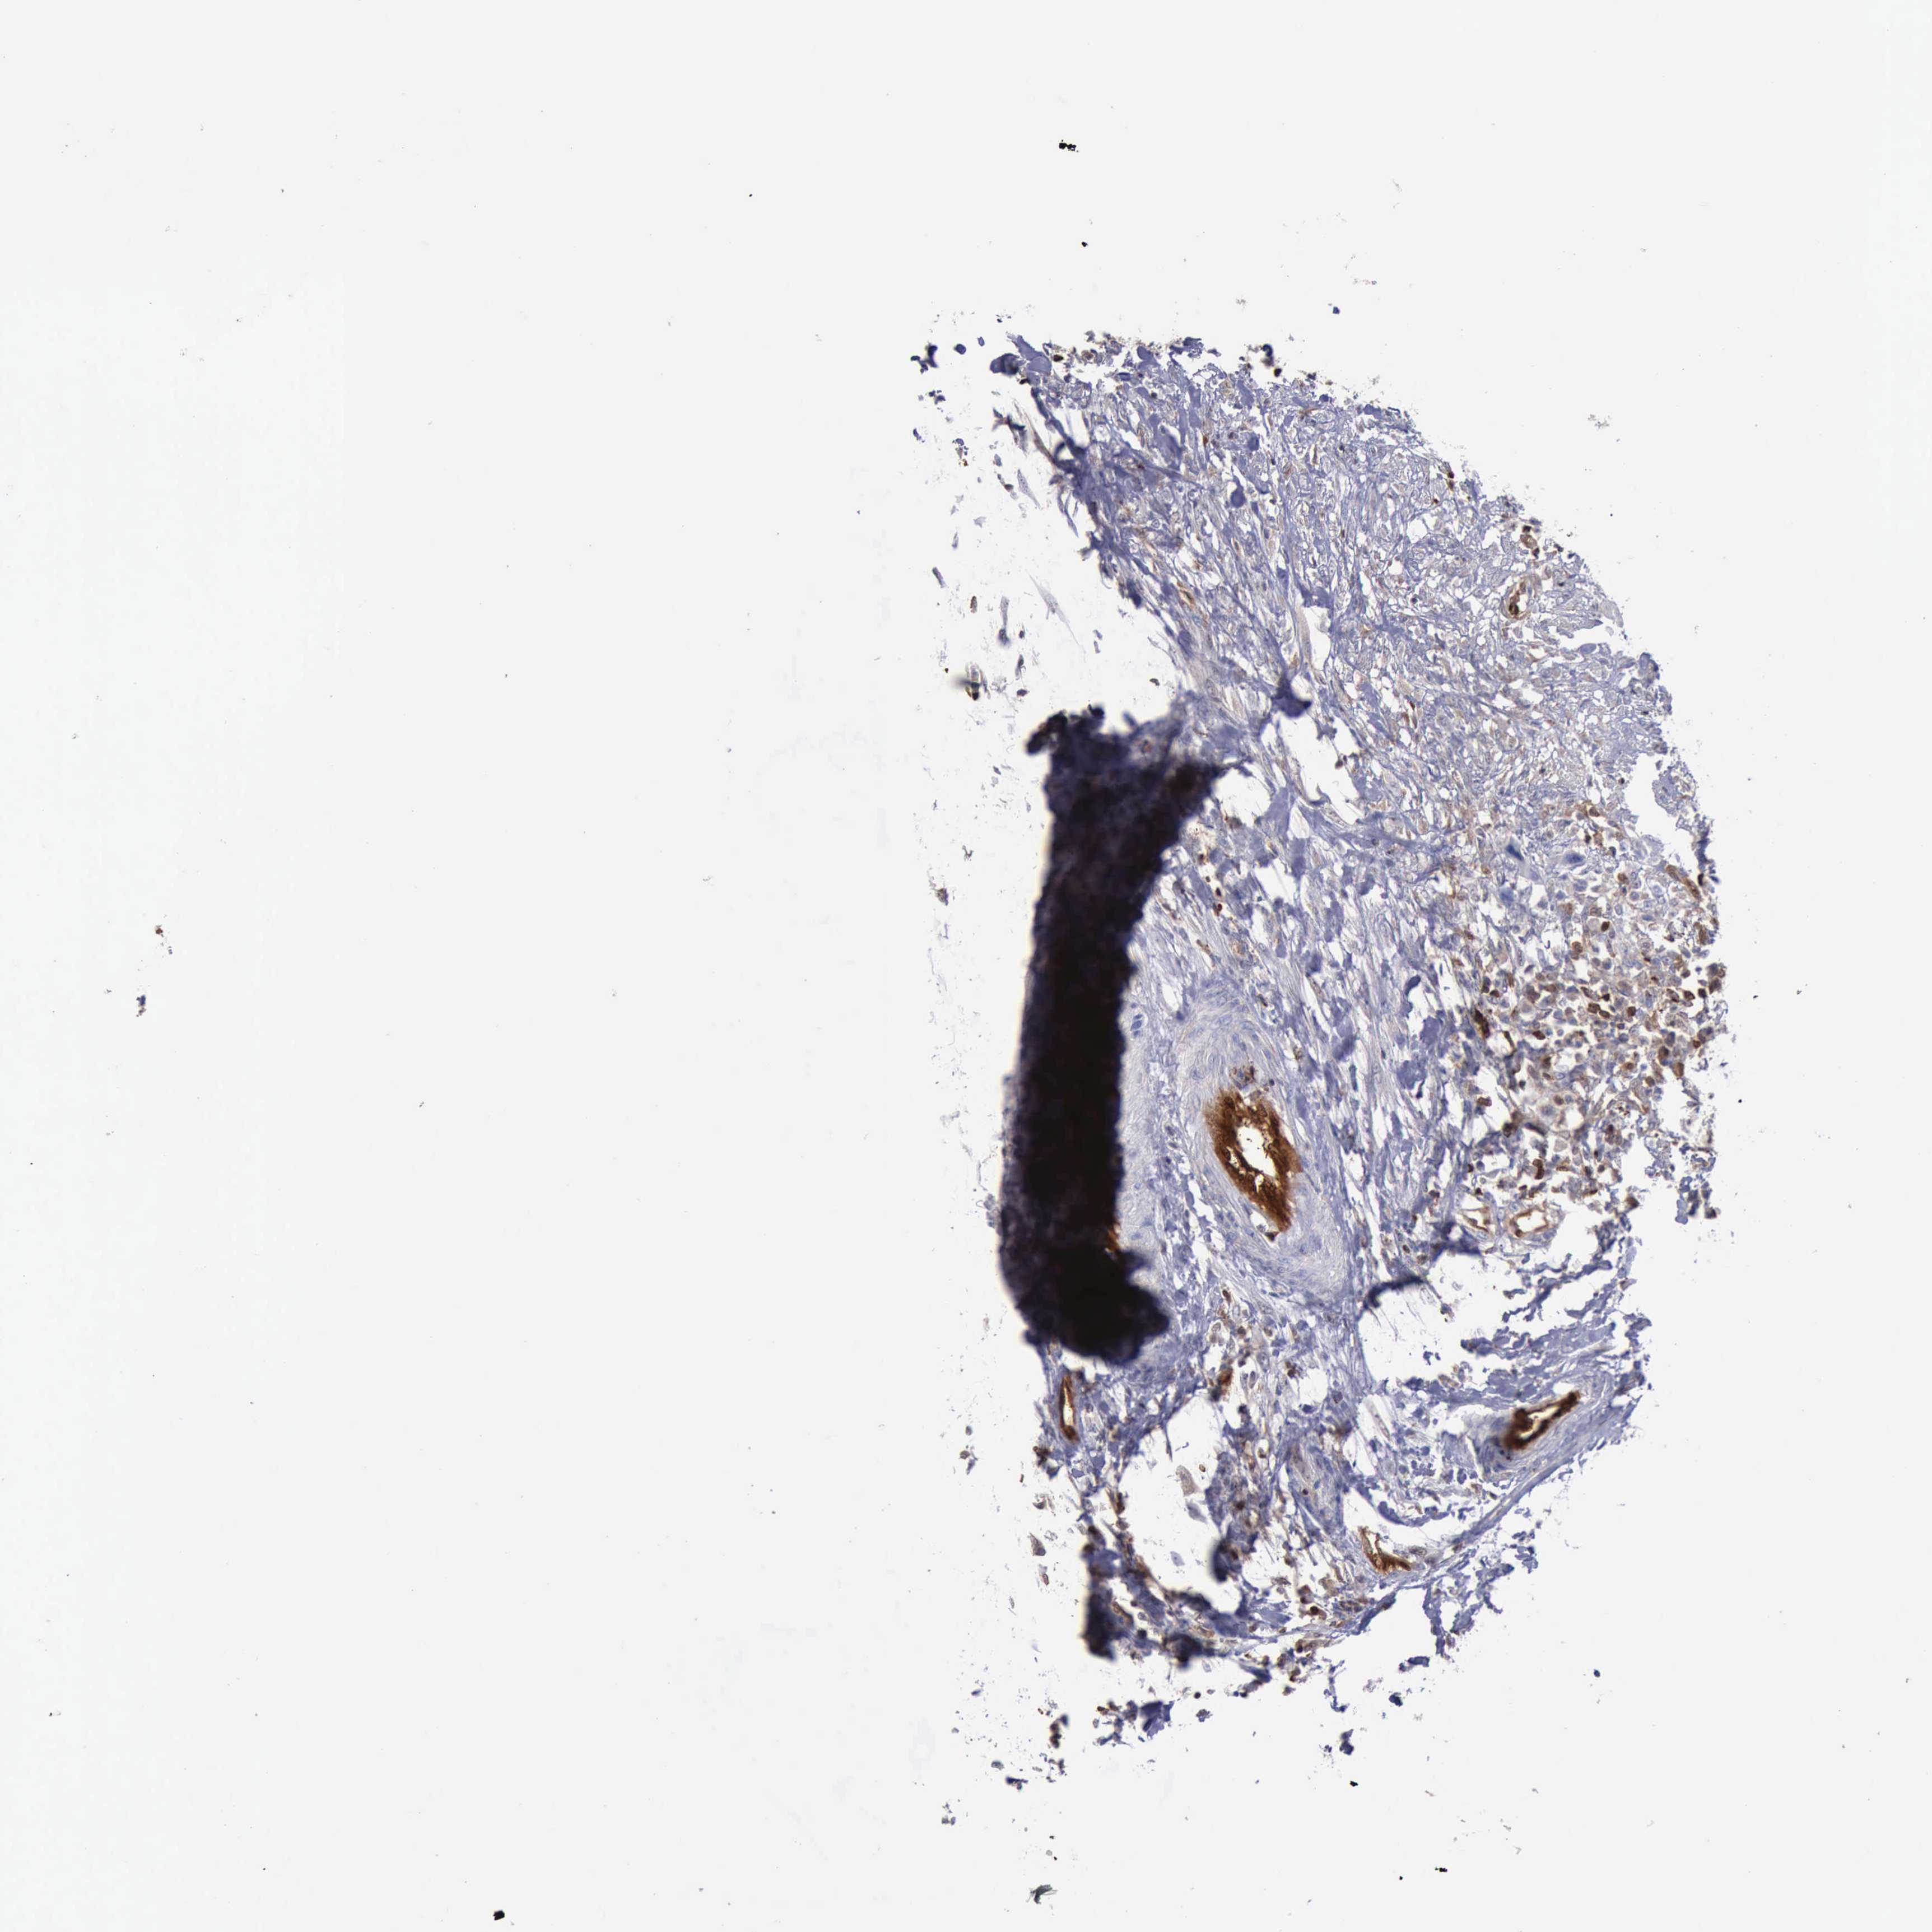

UROTHELIAL CANCER - Protein expressioni

A mouse-over function shows sample information and annotation data. Click on an image to view it in a full screen mode. Samples can be filtered based on level of antibody staining by selecting one or several of the following categories: high, medium, low and not detected. The assay and annotation is described here.

Note that samples used for immunohistochemistry by the Human Protein Atlas do not correspond to samples in the TCGA dataset.

Antibody stainingi

Antibody staining in the annotated cell types in the current human tissue is reported as not detected, low, medium, or high, based on conventional immunohistochemistry profiling in selected tissues. This score is based on the combination of the staining intensity and fraction of stained cells.

Each image is clickable and will lead to virtual microscopy that enables deeper exploration of all samples and also displays staining intensity scores, fraction scores and subcellular localization as well as patient and tissue information for each sample.

Antibody HPA001032

Antibody HPA027214

Antibody CAB037024

Staining

High

Medium

Low

Not detected

Intensity

Strong

Moderate

Weak

Negative

Quantity

>75%

75%-25%

<25%

None

Location

Nuclear

Cytoplasmic/membranous

Cytoplasmic/membranous,nuclear

Urothelial carcinoma, High grade

Urothelial carcinoma, Low grade

Urothelial carcinoma, NOS